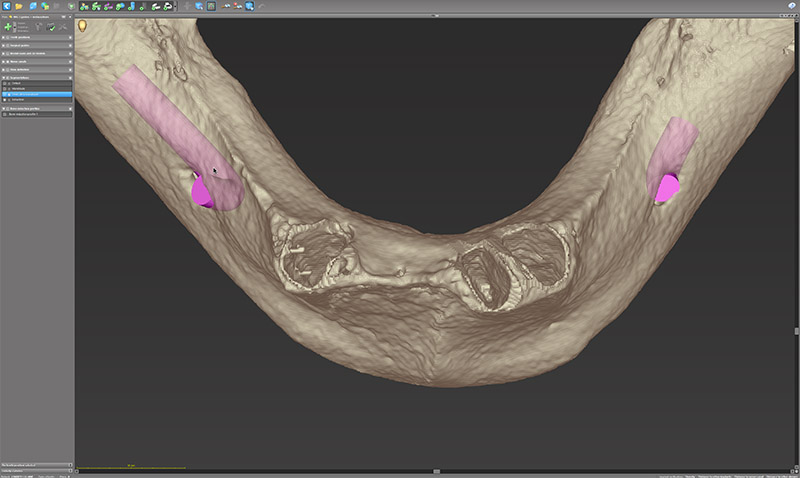

Fig. 10 : l’interface plutôt classique de coDiagnostiX 10 avec les différents volets de visualisation. En bas à gauche, la fenêtre de la reconstruction 3D montre l’os (en beige) et la segmentation des dents (en rouge) issus des fichiers DICOM de la CBCT.

Fig. 11 : mise en évidence des alvéoles.

Cette segmentation par seuillage permet d’extraire virtuellement les dents et mettre en évidence les alvéoles.

Fig. 12, 13 et 14 : le rendu surfacique de la numérisation au format STL de l’empreinte secondaire, la prothèse diagnostique et l’antagoniste.

Sur les données DICOM, sont empilés le rendu surfacique de la numérisation au format STL de l’empreinte secondaire, la prothèse diagnostique et l’antagoniste. Ce dernier est la numérisation du montage directeur polymérisé en prothèse complète conventionnelle.

Fig. 15.

Les implants (Neodent GM Helix Acqua, Straumann Group) et les piliers (Mini GM) sont planifiés selon la prothèse diagnostique validée à l’essayage (fig. 15).